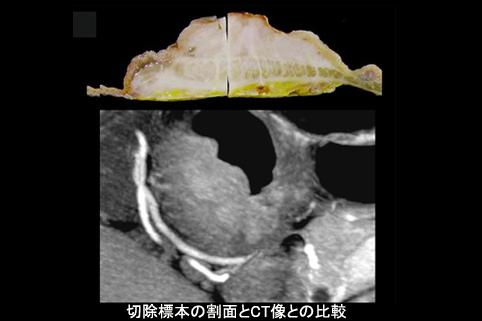

A case of type 5 advanced gastric cancer which developed in the antrum and was diagnosed by multidisciplinary method.

[ Image ID:11390 ]

Malignant epithelial tumor/Adenocarcinoma

Stomach/Antrum

Type 5 Unclassfied type/

40 -

serosa (adventitia)